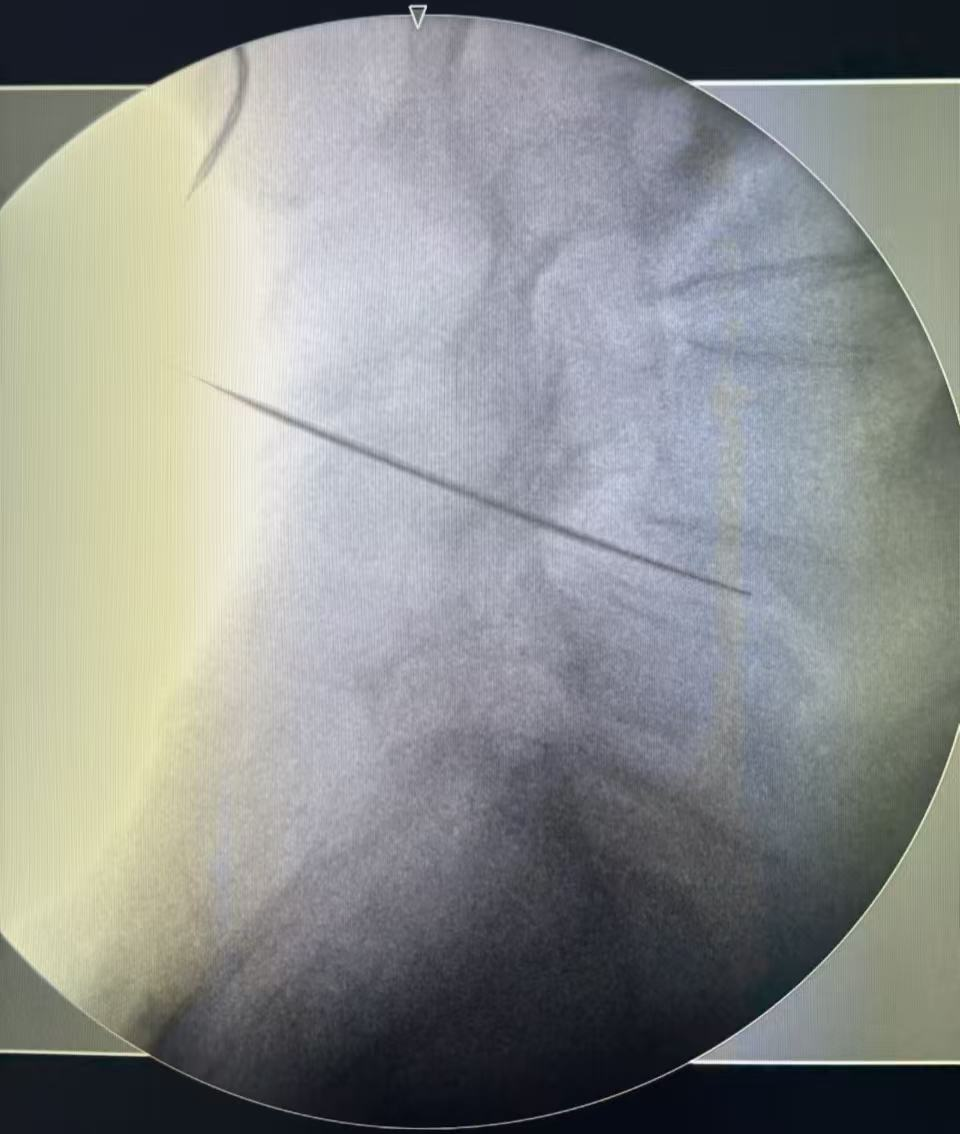

术中透视

腰椎间盘射频消融术并非传统意义上的开刀,而是一场在影像引导下的“精准狙击”。它的原理是什么?简单来说,它是在X线或CT的实时“导航”下,医生将一根直径仅约0.7毫米(类似缝衣针粗细)的射频穿刺针,精准穿刺至患者突出的椎间盘髓核位置。一旦针尖抵达病灶,射频仪通过针尖产生可控的高频电流,使突出部位的髓核组织内的胶原蛋白分子振动、摩擦生热(通常控制在60℃至90℃之间)。这一温度足以使致病的髓核蛋白凝固、变性、收缩,从而体积减小,即刻解除对神经根的压迫。同时,温热效应还能有效消除神经根周围的无菌性炎症,达到“一举两得”的效果。